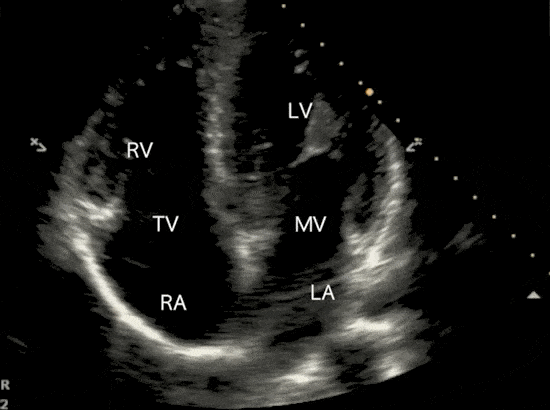

심장판막질환